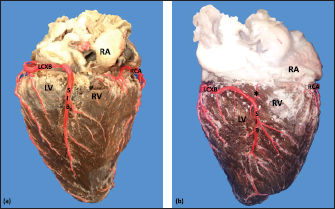

The average weight of the 28 bovine hearts used in our study was 1,534.1 kg. The RCA presented calibers of 5 ± 0.9 mm for the proximal third, 3.4 +/− 0.8 mm in the middle third and 2.3 ± 0.6 mm in the lower third (Fig. 1). The first segment of this artery presented an average of three arterial branches and the second segment had four branches. The RCA ended between the right margin and the crux cordis in 15 cases (53.6%), in 10 specimens (39.3%) it ended in the crux cordis, and in 7.1% in the middle third of the right atrioventricular sulcus (Fig. 2a).

When analyzing its branches, we found the right marginal branch (RMB) in all the hearts, with a proximal caliber of 2.7 ± 0.6 mm and ending in 20 cases in the middle third (71.4%) (Table 1). No significant differences were found between the caliber of the RMB that ended in the middle third compared to those that ended in other segments of the right edge of the heart (p=0.925). The right cone branch (RCB) originated in all cases from the RCA, without finding the presence of a third coronary artery. Its proximal caliber was 2.2 ± 0.5 mm, and its distance from the origin of the aorta was 21.6 ± 8.4 mm. RCB ended on the surface of the conus arteriosus in 20 specimens (71.4%) (Table 1) (Fig. 1). In one case, we observed the presence of anastomosis between RCB and left conus branch (LCB). The atrioventricular node branch (AVNB) had a caliber of 1.3 ± 0.6 mm and originated from the RCA in 25% of the cases and from the LCXB in 75% of the samples (Fig. 2b).

Fig. 1. Anterosuperior view of the heart. (RA): Right atrium; (RV): Right ventricle; (RCA): Right coronary artery; (RCB): Right conus branch.

Fig. 2. Right surface of the heart. Left coronary dominance, subgroup II (a). Left coronary dominance, subgroup III (b). (LV): Left ventricle; (RA): Right atrium; (RV): Right ventricle; (LCXB): Left circumflex branch; (SIB): Subsinusal interventricular branch; (RCA): Right coronary artery; (*):AVNB.

The SIB terminated between the middle and lower thirds (67.8%) (Table 1), presented a termination distance to the apex of 62.9 ± 22.2 mm, and an average of three right and two left branches were observed. The SIB originated mainly from the LCXB and had a proximal caliber of 3.6 ± 0.9 mm, an intermediate caliber of 2.8 ± 0.7, and a distal caliber of 1.9 ± 0.6 (Fig. 2a and b). In the hearts evaluated, 27 (96.4%) showed left coronary dominance. Within this group, the origin of the SIB was observed from the LCXB (subgroup II) (Fig. 2a) in 18 cases (67%), while in 9 cases (33%) it also originated from the SIB of the LCXB, and this last branch ended in the posterior face of the right ventricle (subgroup III) (Fig. 2b). There was only one case (3.6%) of mild right coronary dominance.